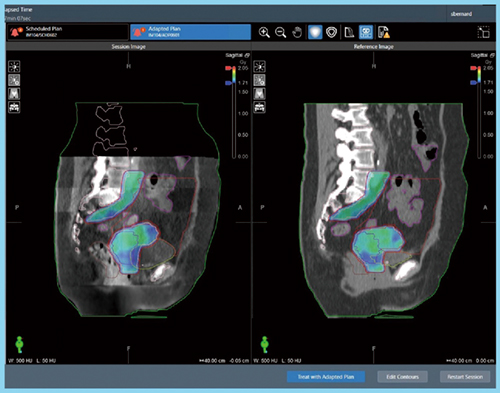

ETHOS Therapyに関する初期の研究では,OARの自動輪郭抽出が高精度に行えることや,non ARTと比較しARTでは計画標的体積(PTV)マージンを縮小でき,正常組織やOARの線量を低減できること,前立腺がんにおいてはすべての患者を15〜20分で治療でき,ARTを日常的に実施可能であることなどが,複数の論文で報告されている。また,骨盤領域におけるScheduled Plan(予定されていたプラン)とAdapted Plan(当日のプラン)を比較した検討では,対象患者の88%でAdapted Planが選択された(図2)。頭頸部においても同様に,15症例中14症例でAdapted Planの方が良好な線量分布が得られたとの報告もある。さらに,別の研究では,複数の疾患部位においてセッションごとにOARの位置と被ばく線量が大幅に変化すること,約65〜100%の症例においてScheduled PlanよりもAdapted Planが選択されることが示された。

図2 Adapted Plan(左)とReference Plan(右)の比較画面例